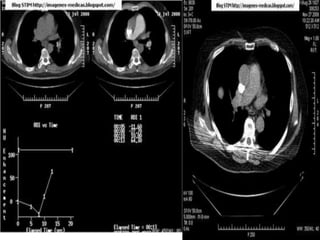

   Smart Prep Previo a la inyección se coloca un ROI

en el vaso de interés por ej aorta desc. . (100-110)

La inyección y la fase de monitoreo comienzan

en simultáneo: se toman imágenes secuenciales

al mismo nivel. El barrido se inicia cuando la

densidad de la luz aórtica supera el umbral. ROI

.o en el (callado aortico).

Roy

Su función es optimizar el contraste y obtener

la fase necesaria para la exploración

Esto depende de que se localice bien el Roy en

el sitio o parte indicada para que el equipo

Pueda medir la escala de hounsfield indica

cuando manda el estudio